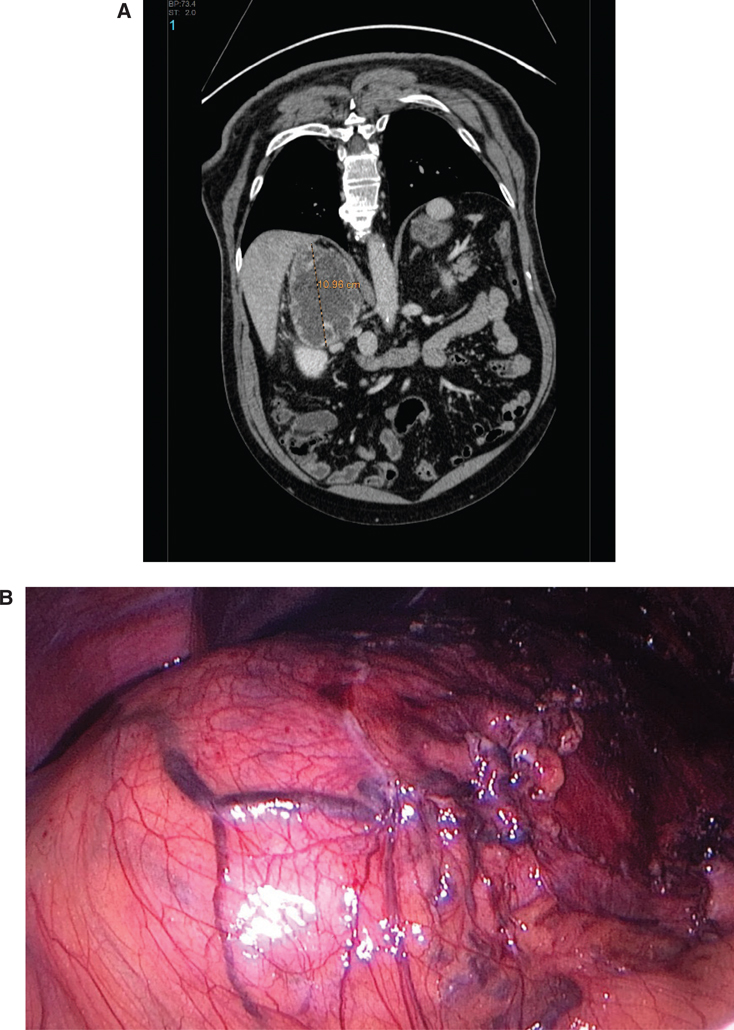

Open adrenalectomy is indicated in patients with large tumors (size greater than 8–10 cm), and for malignant tumors, in order to ensure complete tumor resection, prevent tumor rupture, and avoid local recurrence (Figure 3). The diagnosis of malignancy is based on large tumor size, evidence of local invasion, and presentation with local/regional recurrence(s). The open approach is also recommended in patients who are positive for a germline SDHB mutation or other less common susceptibility gene mutations, such as FH and HIF2α, which are associated with a high rate of malignancy. In all cases of intra-adrenal or extra-adrenal abdominal PGL, laparoscopic surgery should be converted to open operation when dissection is difficult or there is evidence of invasion, adherence, or malignancy. The most used open approaches are the midline and subcostal laparotomies, but a thoraco-phreno-abdominal incision may be necessary in patients with large, locally invasive tumors, particularly on the right side, where this approach offers an excellent pericaval and retro-hepatic view (1126).

Fig 3

Figure 3 CT imaging (A) and surgical imaging (B) of a right pheochromocytoma.